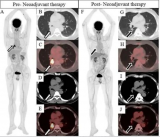

中国临床启动在即,靶向PSMA的抗体核素偶联药物TLX591全球III期研究进入新阶段

Telix Pharmaceuticals公司今日宣布,其针对转移性去势抵抗性前列腺癌(mCRPC)的主要在研疗法TLX591(177Lurosopatamab tetraxetan)的ProstACT全球III期研究已取得重要进展。该研究的第二部分(随机治疗扩展阶段)首位患者已在澳大利亚墨尔本的前列腺癌中心完成给药。ProstACT全球研究是首个将PSMA靶向放射性抗体偶联药物(rADC)疗法与标准治疗(SOC),包括阿比特龙、恩扎卢胺或多西他赛联合使用,并与单独使用标准治疗进行对比的III期试验。第. 2025-12-08 核医学核医药放射性药物